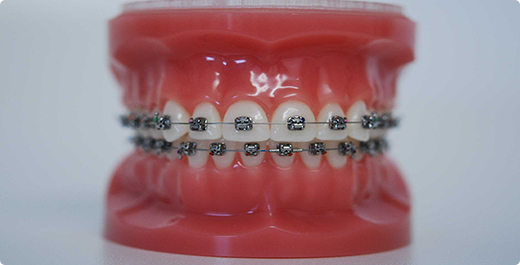

La majorité des traitements orthodontiques ont lieu à l’adolescence. Avant la puberté, nous pouvons encore agir sur la croissance des mâchoires, alors qu’après, seule la position des dents peut-être modifiée. L’appareil le plus fréquent est les brackets, plus communément appelé « bagues », collées sur la face visible des dents. Ils peuvent être métalliques, ou blancs en céramique.

Ces brackets peuvent aussi être collés à l’intérieur pour être invisibles (orthodontie linguale). En fonction des corrections à effectuer, on peut également utiliser des aligneurs qui sont des gouttières transparentes, à porter 22 heures sur 24.

Exemple d’un alignement dentaire

E. est une jeune fille de 13 ans présentant un important décalage entre les 2 mâchoires. Ses incisives supérieures étaient également très inclinées vers l’arrière. Enfin, l’alignement n’était pas parfait.

E. a porté un appareil multibagues, ainsi que des élastiques pendant 24 mois. Elle a été très sérieuse, motivée et très assidue dans ses rendez-vous. Le résultat est très satisfaisant: les 2 arcades dentaires sont en parfaite concordance, les axes dentaires sont corrigés et l’alignement est rétabli.